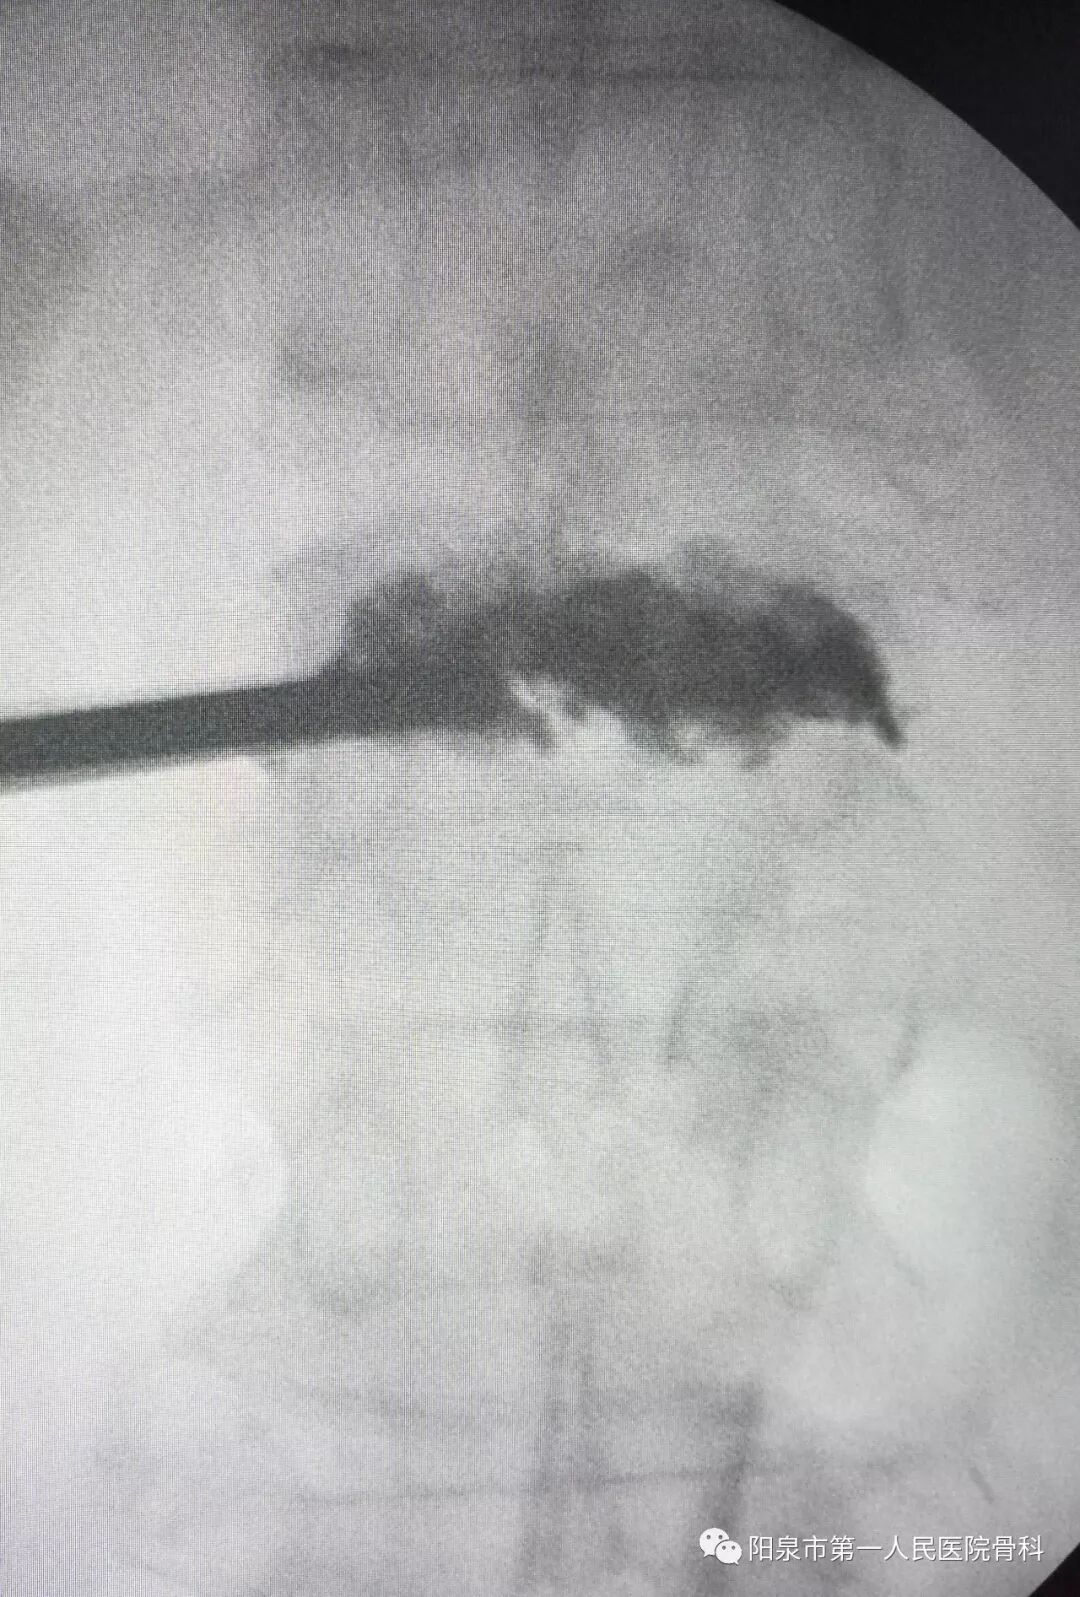

下面为在C臂机透视下观察到的穿刺操作过程,正侧位分别透视来确保正确的穿刺部位。图中黑色直杆为穿刺针。

椎体成型需要哪些器材椎体成形术概述_https://www.jmylbn.com_新闻资讯_第25张

后凸成形术时的球囊撑起显影图像